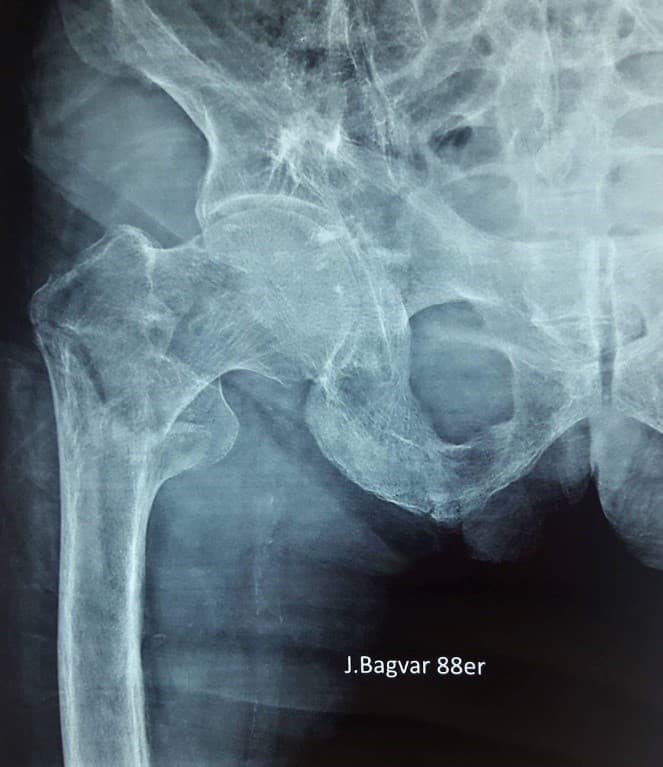

Мэс заслын өмнөх болон дараах зурагууд

Түнхний үе хагас солих мэс засал (Bipolar Hip QRL)image3Түнхний үе хагас солих мэс засал (Bipolar Hip QRL)image4